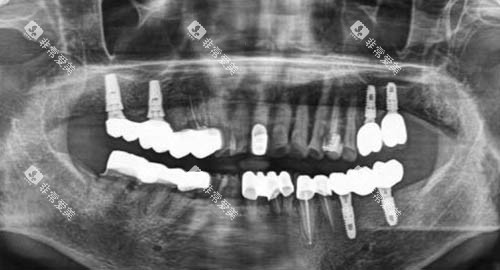

其中,种植牙技术是该门诊部的一大特色。

医生们会根据患者的牙槽骨条件和口腔健康状况,精密地植入种植体,待种植体与牙槽骨紧密结合后,再安装牙冠。

这种修复方式不仅美观自然,而且功能接近真牙,能够为患者带来良好的使用体验。